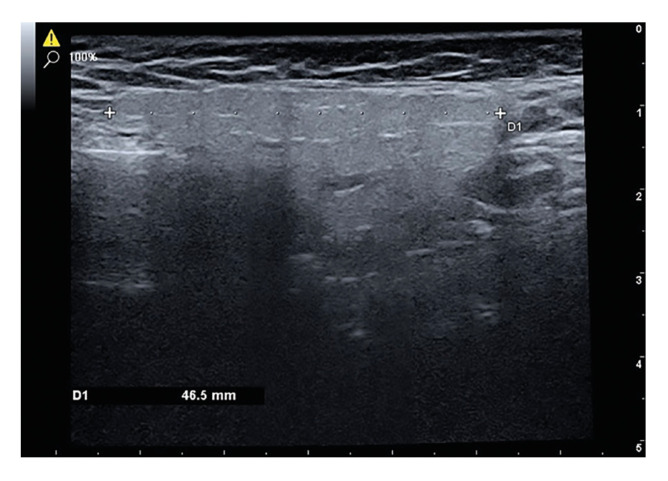

Material and methods: The parotid glands of 38 individuals with diabetes and 38 healthy controls were examined bilaterally using ultrasound to assess parameters of volume, stiffness and microvascularity.

Results: A statistically significant increase in parotid gland volume and a statistically significant decrease in microvascularity were observed in diabetic patients. Furthermore, a statistically significant increase in parotid gland volume was noted in diabetic individuals who were using antidiabetic drugs in comparison to non-users. A significant negative correlation was identified between the duration of exposure to diabetes and microvascularity.

Conclusions: Ultrasonographic imaging can be used to assess the dimensions and microvascularity of the parotid gland.